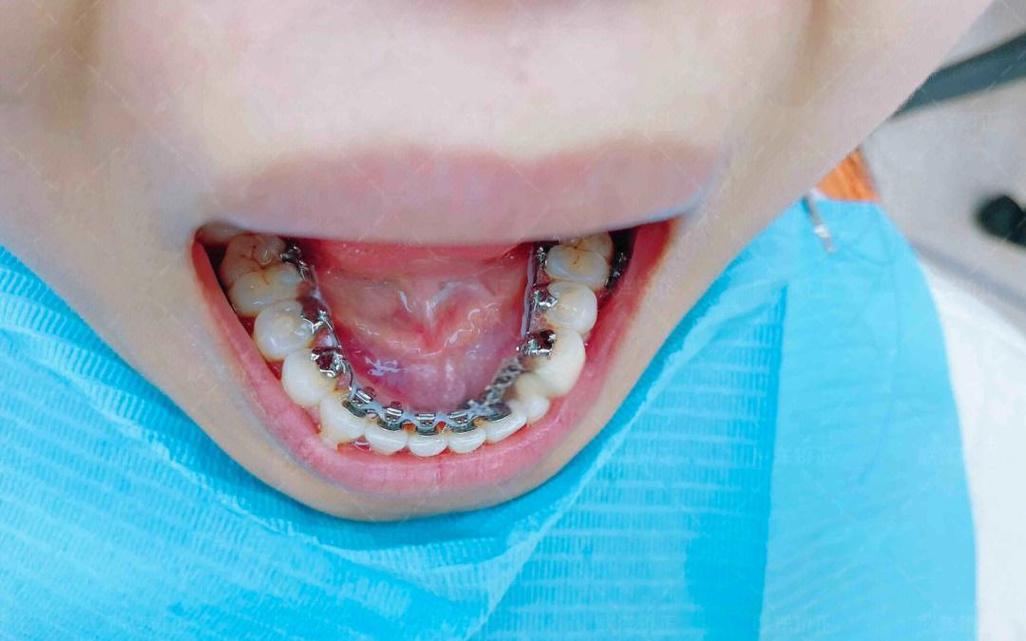

- 弓丝调整:医生会使用钳子(如细丝钳、结扎丝钳)对偏移的弓丝进行弯曲、调整,使其与所有托槽槽沟完全贴合,若弓丝向颊侧偏移,医生会将颊侧弓丝向舌侧轻弯;若弓丝末端过长,会修剪并重新回弯末端。

- 更换弓丝:若弓丝已发生永久性变形或疲劳,医生会根据治疗阶段更换新的弓丝(如从镍钛丝更换为不锈钢丝,或调整弓丝尺寸)。

- 托槽重新粘接:若弓丝偏移是由托粘接位置偏差导致的,医生会拆除原托槽,重新定位并粘接,确保弓丝与牙列完全贴合。